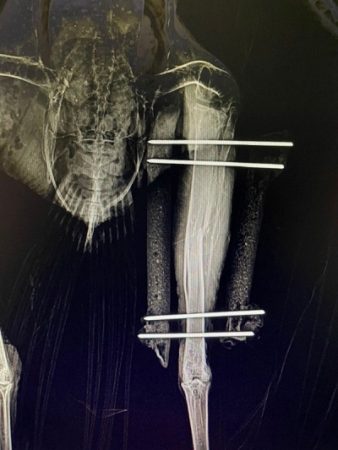

Curious how we fix a broken bird leg?

During examination, it was found that this bird’s right tibiotarsus (one of the leg bones) was fractured, likely from a vehicle interaction.

An external fixator was placed to stabilize the break, and it will be removed in a staged process over the next 4 weeks. With these pins in place, the patient is able to bear weight on the leg while the fracture heals!